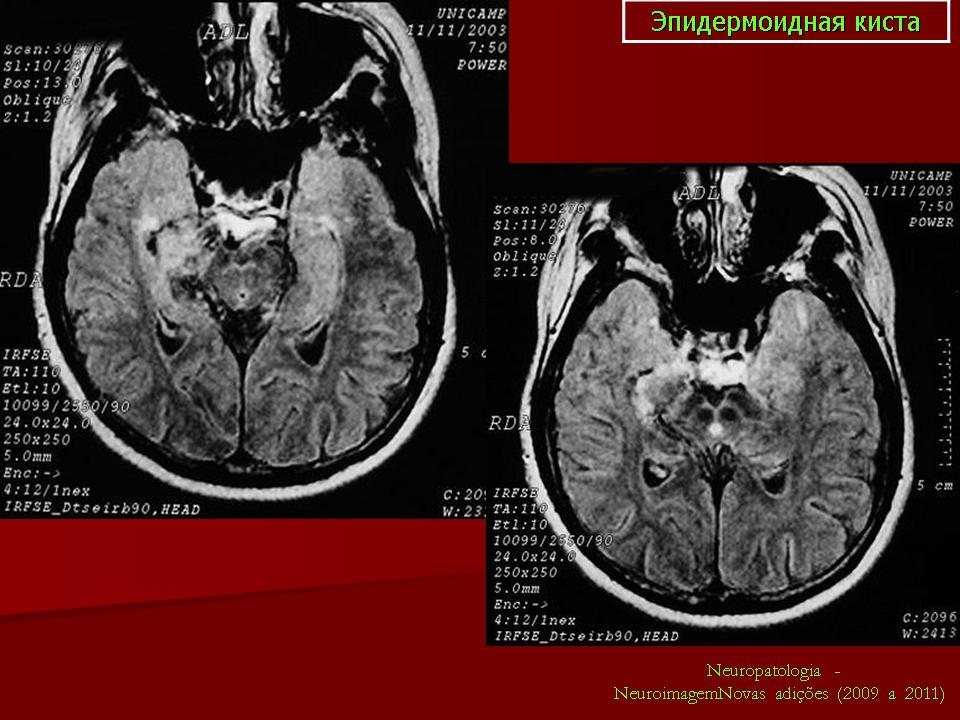

Эпидермоидная киста.

ID: 5664 Epidermoid cyst (small pre-pontine) Dr Frank Gaillard - 5 Mar 2009 MRI demonstrates a small region in the pre-pontine cistern with distorti...

ID: 9772 Epidermoid cyst - cerebellopontine angle Dr Frank Gaillard - 23 May 2010 Characteristic appearance of an epidermoid cyst in the cerebellopon...

ID: 2609 Epidermoid cyst - cerebellopontine angle Dr Frank Gaillard - 7 May 2008 This patient had a right sided cerebellopontine angle mass (shown to be ...

ID: 4366 Epidermoid cyst - cerebellopontine angle Dr Frank Gaillard - 14 Aug 2008 Selected images from an MRI demonstrating both typical appearances and l...

ID: 13721 Epidermoid cyst - cerebellopontine angle Royal Melbourne Hospital - 10 May 2011 This case demonstrates typical appearances of a large cerebellopontine a...

ID: 15137 Epidermoid cyst - cerebellopontine angle Dr Frank Gaillard - 25 Sep 2011 This case demonstrates typical location and appearances of an epidermoid...

ID: 20385 Epidermoid cyst - involving pre-pontine and basal cisterns and left CP angle Dr Ashutosh Gandhi - 16 Nov 2012 Related articlesepidermoid cyst